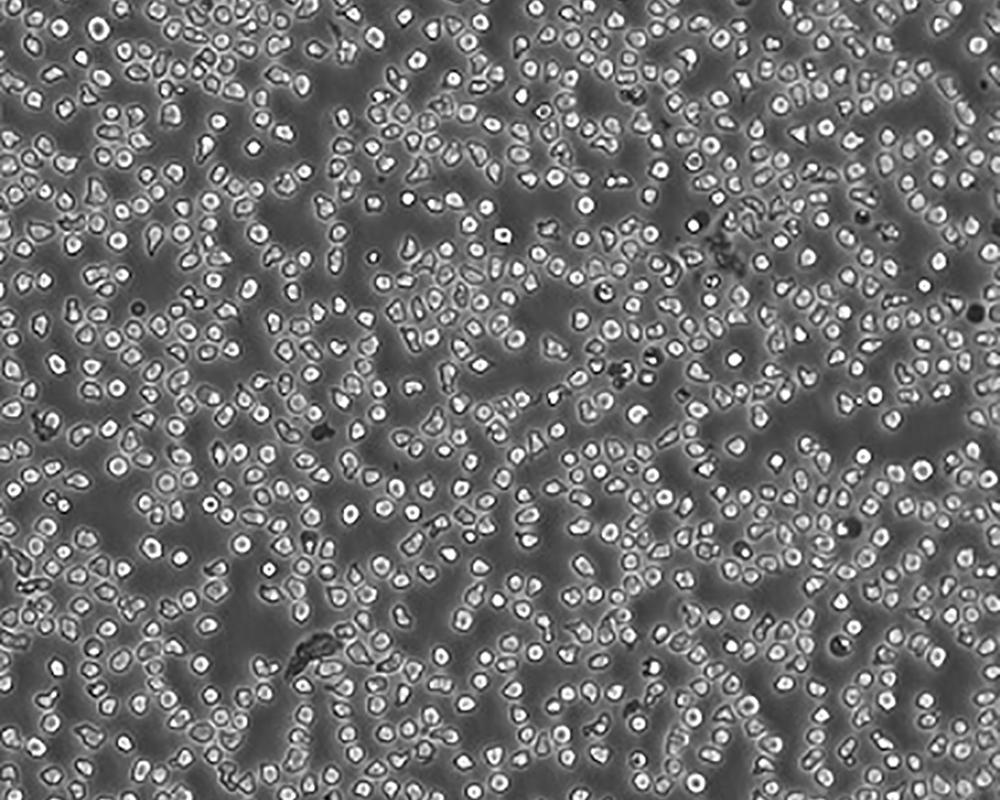

生長特性 suspension

形態特征 lymphoblast

細胞描述 一位套細胞淋巴瘤患者的巨細胞變種顯示白血病轉變,從其外周血單核細胞出發建立了MCL細胞株JeKo-1。 JeKo-1細胞EB病毒陰性,并表達一種B細胞表型的IgM。 細胞過表達cyclin D1, Bcl-2, c-Myc 及 Rb 蛋白。 Bcl-1/J(H)基因重排得到了PCR證實。 JeKo-1細胞在SCID小鼠中高成瘤。 [PubMed: 9753063]